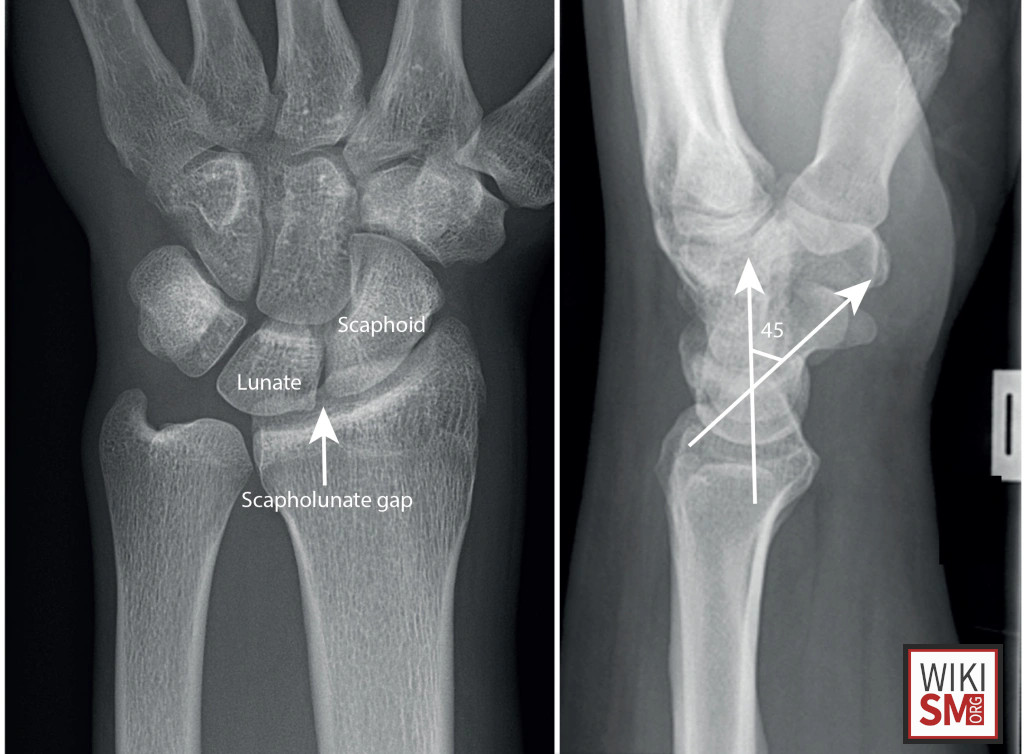

Expand your clinical knowledge with WikiSM.org —a comprehensive resource for sports medicine, MSK exams, and rehabilitation—and MedEdCases.com for real-world, case-based emergency medicine learning